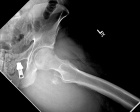

Patient is a 50 y/o male who presented with an enlarging L. thigh mass over past six months with recent onset of pain; PMH: unremarkable

PE: Large firm mass in medial compartment of L. prox. thigh w/ superficial varicosities; no TTP; NVI

Zoom image: Radiological image Radiological image.